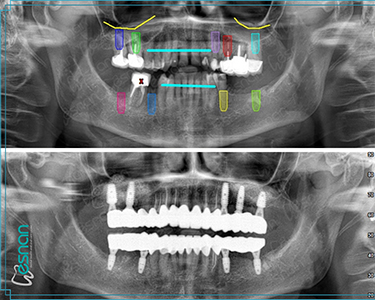

Oral, dental, and maxillofacial radiology is a crucial element in comprehensive dental care. It utilizes various imaging techniques, such as periapical radiographs, panoramic radiographs, cone beam computed tomography (CBCT), and occlusal radiographs. These tools provide valuable insights into the underlying structures of the mouth, teeth, and jaws, allowing dentists to diagnose and treat a wide range of conditions, including dental caries, periodontal disease, infections, tumors, and developmental abnormalities. Early detection and accurate diagnosis through oral, dental, and maxillofacial radiology can significantly impact treatment outcomes and improve overall oral health.

Planning for dental implants

Our Radiology Unit in Istanbul is equipped with state-of-the-art technology to provide comprehensive dental imaging services. We offer a range of examinations, from standard panoramic X-rays to more advanced 3D imaging like CBCT scans. These services are a core component of Radiology – Intraoral Diagnosis in Turkey, supporting detailed assessment and precise treatment planning.

Each examination listed above serves a specific purpose in dental diagnostics. Panoramic X-rays provide a broad view of your teeth, jaws, and surrounding structures, while intraoral radiography offers detailed images of individual teeth. Cephalometric X-rays assess facial growth and development, and CBCT scans provide detailed 3D images for complex cases like implant planning and oral surgery. Our experienced team is dedicated to utilizing these technologies to deliver precise and personalized care for every patient.